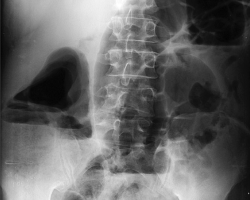

L’arthrose de hanche ou coxarthrose est une maladie fréquente, consistant en une lésion de l’articulation de la hanche, cartilage et os, d’origine mécanique. […]